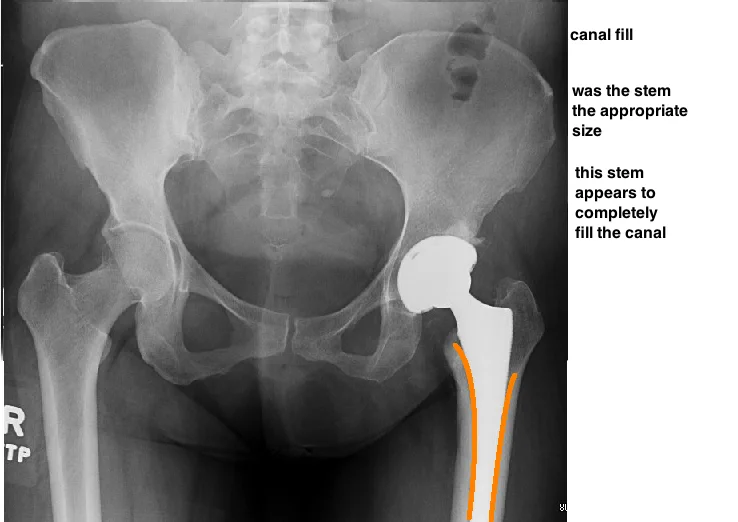

THEN EVALUATE STEM PLACEMENT.